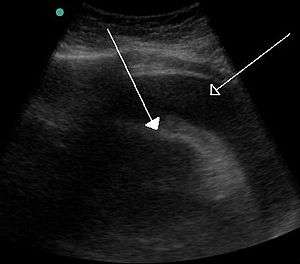

Bladder tamponade is obstruction of the urinary bladder outlet due to heavy blood clot formation within it.[2] It generally requires surgery.[2] Such heavy bleeding is usually due to bladder cancer.[3]